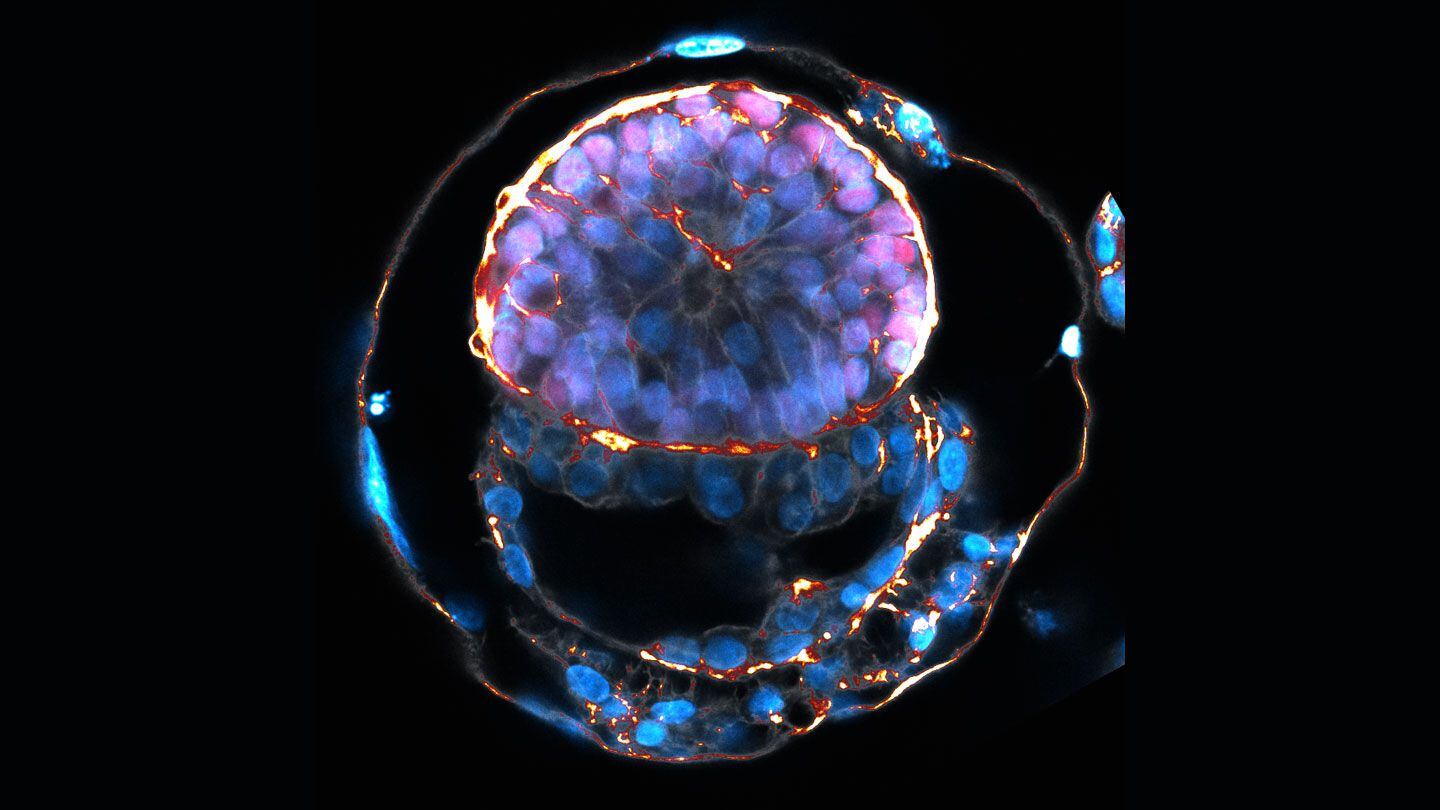

Este avance científico sin precedentes se basa en la creación de embriones sintéticos desde células madre Gentileza: Jacob Hanna/Instituto Weizmann de Ciencias

Este avance científico sin precedentes se basa en la creación de embriones sintéticos desde células madre Gentileza: Jacob Hanna/Instituto Weizmann de Ciencias

Las células fueron tratadas únicamente con productos químicos, sin necesidad de modificación genética, dijo Jacob Hanna, del Instituto Weizmann de Ciencias NATURE

El equipo de Hanna fue el primero en comenzar a describir métodos para generar células madre humanas vírgenes

El equipo de Hanna fue el primero en comenzar a describir métodos para generar células madre humanas vírgenes

Un modelo de embrión basado en células madre humanas en el día 8. El amarillo marca el saco vitelino y el rosa es el trofoblasto (Jacob Hanna/Instituto Weizmann de Ciencias)